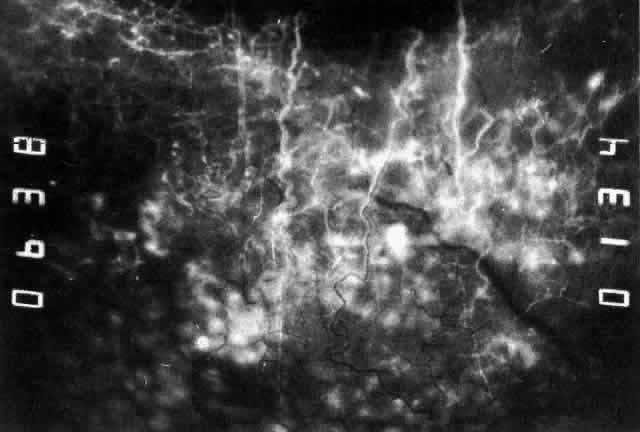

can be mistaken for malignant melanoma.  Fig. 19. Anterior necrotizing scleritis. The eye was removed because of loss of

vision and intractable pain. No form of steroid was given to this patient

because of a severe Pseudomonas infection of the chest. (Courtesy of Professor N. Ashton) Fig. 19. Anterior necrotizing scleritis. The eye was removed because of loss of

vision and intractable pain. No form of steroid was given to this patient

because of a severe Pseudomonas infection of the chest. (Courtesy of Professor N. Ashton)

not be performed. Scleritis usually affects the anterior segment of the eye, possibly because

this is the area with the best blood supply, but with sluggish flow

through the vessels (Fig. 19). The sclera is thickened and roughened in the affected area, which appears